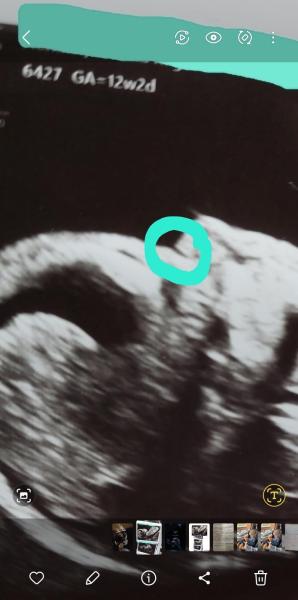

Hallo, ich habe hier ein aktuelles Ultraschallbild und möchte gerne in die Runde fragen, ob ihr diesen Riss im Nasenrücken auch seht ? Bei mir wurde sicherheitshalber ein NIPT Test gemacht, weil das Nasenbein wohl nicht gut darstellbar war. Die Praxis hat 3 Wochen Urlaub und das Ergebnis vom NIPT liegt erst in 3 Wochen vor. Ich frage mich, ob so ein Riss durchaus mal vorkommen kann oder mit Trisomie 21 im Zusammenhang stehen könnte. Das Baby war während der Messungen sehr aktiv und hat sich viel gedreht und bewegt.

Bild zu 12+2 SSW Darstellung der Nase - Schwanger - wer noch? Rund um die Schwangerschaft

Er war sich halt sehr unsicher ob das Nasenbein vernünftig darstellbar ist, weil sich das Kind so viel bewegt hat und man daher nicht so richtig gut schalten konnte. Er hat mir sicherheitshalber zum NIPT Test geraten wegen dem Nasenbein und meinte aber auch, dass die Wahrscheinlichkeit gering ist.

Da ist kein Riss!!! Genauso wie die schwarzen Stellen im Kopf und Bauch keine Luft sind und dort nichts kaputt ist. Das ist ein Blutgefäß oder Bindegewebe. Beides gehört da hin. Ist also völlig normal  Es hat einen Grund wieso Ärzte 6 Jahre studieren, mind. 5 Jahre Facharzt machen und dann oft noch spezialisierte Weiterbildungen ;)

Mir geht es um diese Stelle. Ich habe absolut keine Ahnung davon, die Stelle sieht aber irgendwie seltsam aus.